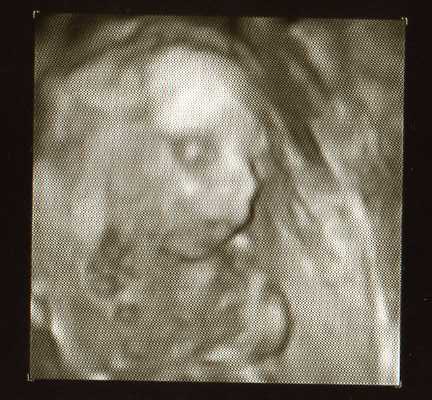

Oto portrety naszego Kubusia z 20 tygodnia:-)

Waży 340g

• 4d.jpg

4d.jpg